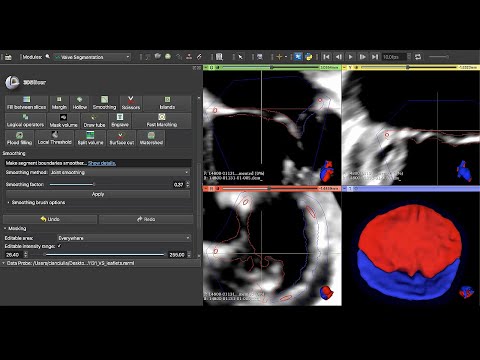

👌Embarking on a mission to become more familiar with creating #3Dprint in @3DSlicerApp ! Example of 🫀 from a simple threshold and then using the remove islands and smooth function to optimize. #yesCCT @mmamas1973 @iamritu @purviparwani @tiffchenMD @KidsAtColumbia @ColumbiaMed

We are thrilled to publish our description of #SlicerHeart, a open source, cardiac-focused image processing extension for @3DSlicerApp that has now been downloaded over 44,000 times. frontiersin.org/articles/10.33…